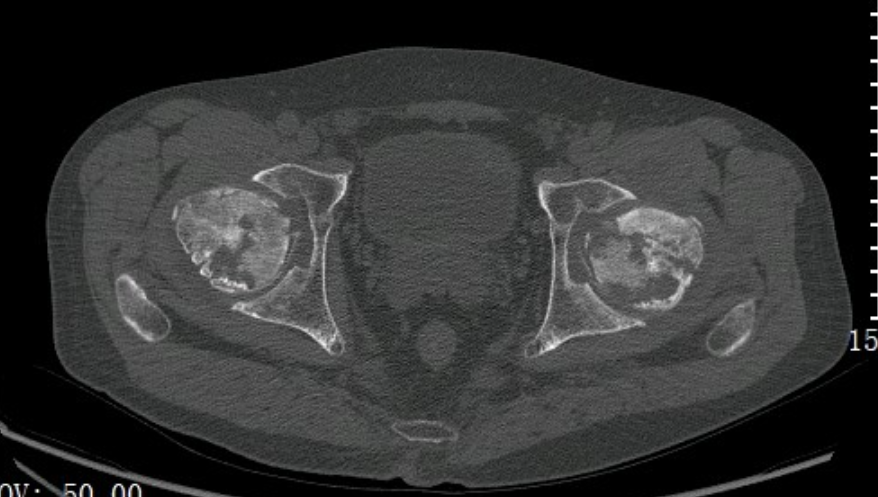

考虑患者有长期激素使用情况,高度怀疑出现股骨头坏死。

从片子上可以看到,双侧股骨头已经塌陷变形,关节间隙也变的很窄了,已经到股骨头坏死Ⅳ期(最严重的一期了)。只有通过人工髋关节置换术才能解决问题。